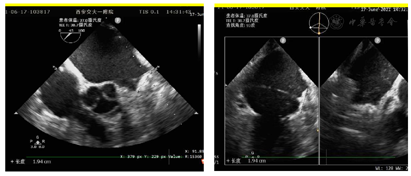

入院后常规检查未见明显异常,心动超声提示左房增大伴二尖瓣中量反流,LA前后径40mm。该患者入院后根据CHA₂DS₂-VASc评分及HAS-BLED评分来进一步评估其卒中及出血风险,该患者CHA₂DS₂-VASc评分4分,HAS-BLED评分3分,属于高卒中及高出血风险患者。因该患者仍有心悸症状发作,且多次服用抗凝药物后有上消化道出血表现,故向患者及家属建议行房颤射频消融及左心耳封堵一站式手术。术前进一步行食道超声明确左心耳是否存在血栓及形态,术前食道超声提示心耳内未见血栓,心耳偏小,在90°上可能呈反鸡翅型(表1)。

由于该患者术中需要精确房间隔穿刺,因此采用常规全麻+TEE指导术式,TEE指导下选择了偏下、偏前的房间隔穿刺部位(图5)。

穿刺成功先行房颤射频消融治疗,消融完成后更换左心耳封堵鞘,以猪尾导管保护于RAO30° CAU25°造影,左心耳形态充分暴露,可以观察到心耳属于反鸡翅形状。内部梳状肌较发达,深度较浅。DSA测量开口18mm,深度19mm,与CT测量结果类似,考虑选择24mm watchman封堵器,首选X3轴向进行封堵。术中在猪尾导管的保护下,逆时针旋转输送鞘,尽量将输送鞘送入上叶。稳定输送系统,体外预借2mm深度,送入封堵伞,逆时针旋转稳定输送鞘,术中缓慢释放封堵伞,释放后稳定5分钟后造影提示封堵完全,上缘轻度露肩,行TEE检查未见残余分流,压缩比测量12.5%~21%(图7,图8),经牵拉测试稳定,符合PASS原则,决定释放封堵器,释放后再次造影提示封堵完全(图9)。术后患者顺利清醒,术后6小时检测无心包积液,加用达比加群110mg 2次/天;术后第五天出院。